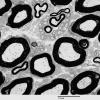

PERIPHERAL NEUROPATHY

2 NORMAL AXON